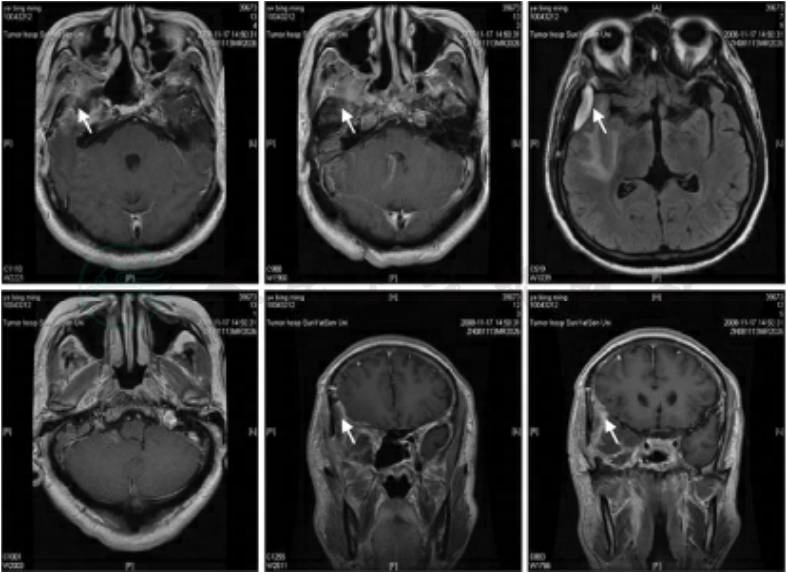

现病史:患者于就诊前半月无明显诱因出现右耳听力下降症状,偶有头晕,伴记忆力下降,无面麻,耳鸣,无视朦及复视等症状。后就诊当地医院,行鼻咽活检考虑“鼻咽癌”,后来我院门诊就诊并完善检查,鼻咽MRI结果提示蝶窦内、右侧筛窦、右侧海绵窦以及右侧颞叶肿物,考虑“脑膜瘤”可能。由于难以确诊,申请全科会诊。

初步分析:考虑鼻咽癌可能性大。患者为中年男性,广东人,临床检查可见鼻咽部左侧隐窝处结节状肿物(图1),血清学检查示EB病毒抗体阳性;患者就诊当地医院,已经行鼻咽病理活检,病理结果初步考虑为“鼻咽癌低分化鳞癌”。

共同决策在一定的程度上也使医生从许多难以决定的选择中解脱出来,医生不再单独承担相关的风险。就患者而言,积极参与共同决策既是自我尊重,也对疾病的发展有思想准备(特别是恶性疾患);就医生而言,在进行医疗工作过程中也更加得到患者的理解和支持,亦有利于临床工作的顺利开展。现代医学是讲究证据的医学,临床决策的实践不可能偏离这个轨道,从这个方面来说共同决策过程就是循证医学实践的过程。共同决策提供的是一种新的医患决策关系模式,患者参与临床决策既是法律的需要也是伦理的需要,共同决策体现了以人为本、以患者为中心的医疗服务理念,尤其在现今的国内医疗环境下,更加值得提倡。在共同决策里二者同等重要,他们之间是一种协作关系而非对抗的。共同决策里,医生还担负着教育患者的任务,那就是在共同决策进行的过程中首先向患者解释,讲解危险,收益等情况,使患者要有参与决策的基本知识和思想基础。当然,医生的讲解和解释应该是客观的而不能带有主观偏见甚至是诱导,否则共同决策就失去了其本意。诊断二:不排除脑膜瘤可能。患者在我院行颅脑以及鼻咽MRI结果提示蝶窦内、右侧筛窦、右侧海绵窦以及右侧颞叶肿物(如图2)。临床阅片分析,考虑脑膜瘤可能。

图2 治疗前磁共振表现:右侧颞叶可见肿物(箭头所示为肿瘤所在)

图3、图4为治疗后图像。

图4 术后放疗后磁共振表现:右侧颞叶呈术后改变,未见明显肿物